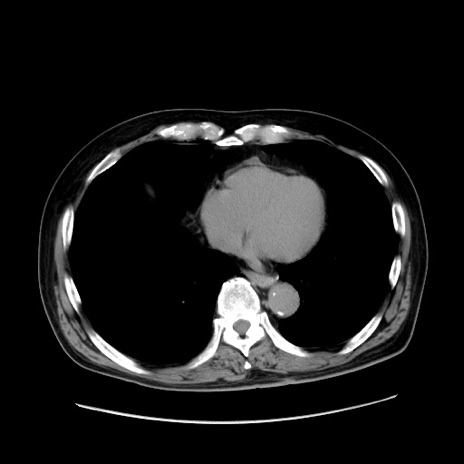

症例30(横断像)

冠状断像

【症例】80歳代男性

【現病歴】約6時間前から臍下部痛が出現。次第に腹部膨隆・背部痛も生じてきたため来院。背部痛の場所は変化しない。

【身体所見】意識清明、BT 36.3℃、BP  131/87mmHg、P 87bpm、SpO2 100%(RA)、臍周囲自発痛・圧痛あり、反跳痛なし、自発痛部位に一致して板状硬あり、腹部膨隆、腸雑音減弱、CVA tenderness両側陰性。